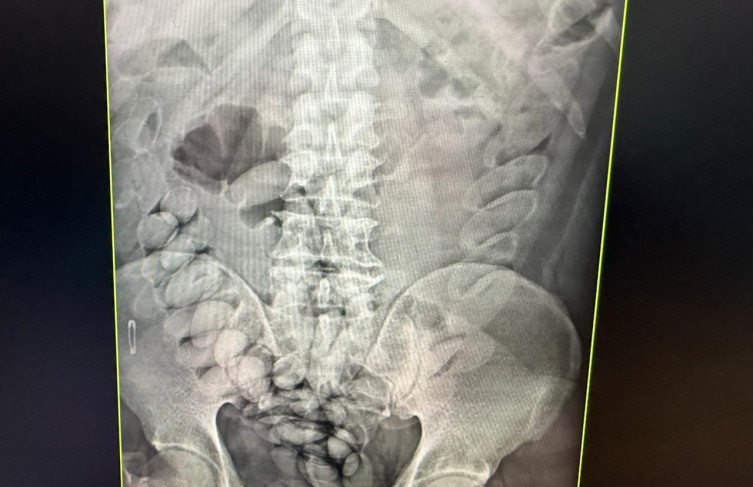

Exames de raio-x comprovaram a ingestão de entorpecente

Os indivíduos foram encaminhados ao hospital, onde exames confirmaram que haviam ingerido cápsulas com o entorpecente. Após expelirem a droga, eles foram levados à Polícia Federal para prestar depoimento e, em seguida, foram presos. Ao todo, cerca de 4 quilos da droga foram apreendidos.